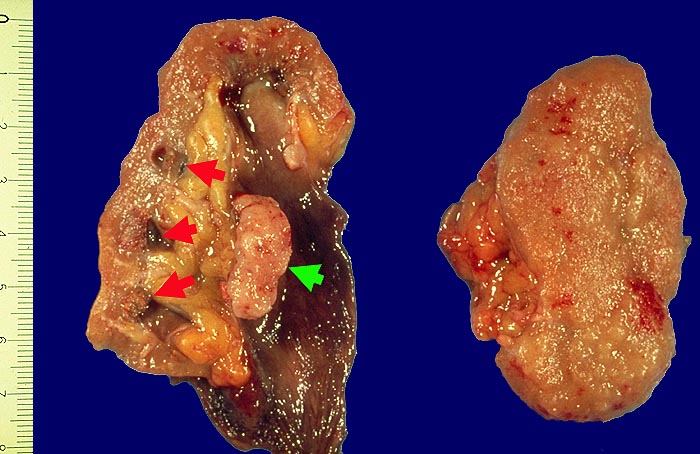

AP/ Urothelkarzinom bei Phenacetinabusus

Urothelkarzinom bei Phenacetinabusus

Pathomorphologisch unterscheiden sich Urothelkarzinome bei Phenacetinabusus nicht von sporadischen Urothelkarzinomen abgesehen von ihrer bevorzugten Lokalisation im Nierenbecken und der allenfalls ausserhalb des Tumors in der Harnwegsschleimhaut nachweisbaren Kapillarosklerose.

Morphologische Merkmale:

• Solider Tumor mit fokalen Entzündungsinfiltraten.

• Polymorphe Tumorzellen mit unscharfen Zellgrenzen und bläschenförmigen (=vesikulären) Kernen.

• Zahlreiche Mitosen.

• Ureter mit verdickten Kapillaren (Kapillarosklerose).